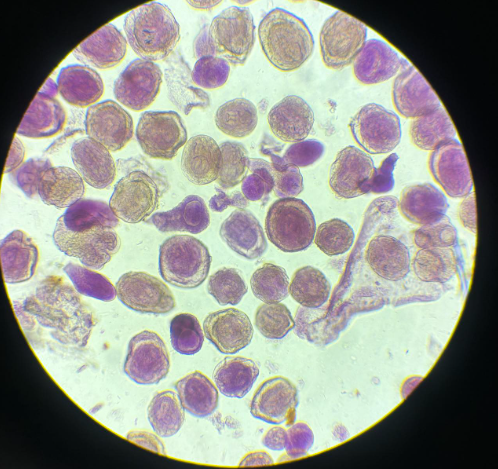

plasmodium falciparum stadia schizogonii krwinkowej

plasmodium falciparum stadia schizogonii krwinkowej